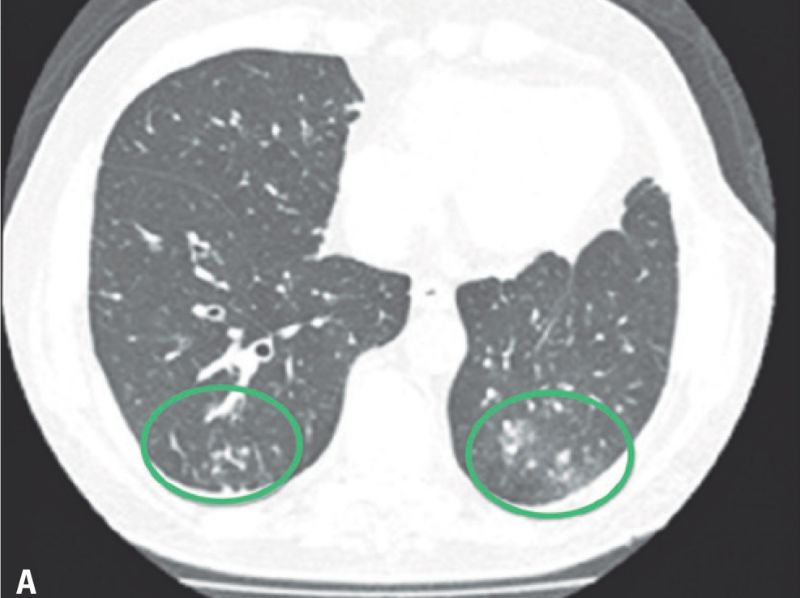

患者是一名73岁的老年男性,左大腿存在黑色素瘤病灶。病人在发病早期就接受了局部切除治疗,并在日后的过程中坚持随访。直到术后第8年,病人检查出了肺部的黑色素瘤转移病灶,其开始使用达卡巴嗪和伊匹木单抗进行治疗,但是病情的进展过程并没有被抑制,因此,病人开始使用帕博利珠单抗每3周2mg/kg的方案进行治疗。但是在第一次治疗后的14天时,病人开始出现干咳(无其他症状),CT检查显示其双侧肺部都出现了磨玻璃样改变。病人被确诊为帕博利珠单抗导致的肺炎,并迅速接受了1mg/kg强的松联合抗生素的治疗,万幸的是病人的肺部症状在用药治疗后出现 了明显的好转。2个月后,病人的肺部炎症反应被完全治愈,并对持续进行的帕博利珠单抗治疗表现出了良好的耐受性。

患者是一名54岁的老年男性,被确诊为肺大细胞神经内分泌癌,并且已经出现了转移。最初,病人使用了卡铂和紫杉醇进行治疗,随后又使用了顺铂和依托泊苷,同时接受了定向放疗。但是传统治疗的疗效并不理想,病人很快出现了中枢神经系统和肝脏的转移,因此帕博利珠单抗每3周2mg/kg的治疗方案再次临危上阵。在治疗5个疗程后,病人开始出现呼吸困难和咳嗽(无发热),氧饱和度仅为84%,CT检查显示其双肺出现了磨玻璃样变性。因此,病人开始每6小时使用哌拉西林-他唑巴坦4.5g的甲羟泼尼松2mg/kg进行治疗,在治疗开始后的24小时内,病人的肺部病情就出现了好转,治疗1周后的CT检查显示,病人肺部原先的浑浊阴影几乎全部消失。

该患者是一名70岁的老年男性,患有转移性肺表皮样癌合并多发性肝损伤。因患者的基本状态并不适用于铂类化疗,因此病人直接使用了纳武利尤单抗(Nivolumab)每2周3mg/kg进行治疗。在治疗4个疗程后,病人开始出现精神混乱、呼吸困难和干咳等症状(无发热),其血氧饱和度也跌到了74%,血细胞计数正常。CT检查显示其肺部出现了磨玻璃样浸润区。因考虑患者可能出现了免疫相关性的肺炎,其开始接受甲基强的松龙每8小时60mg的治疗,抗生素治疗也同步进行。仅仅在数小时内,患者的病情就出现了好转,并在治疗3天后就完全治愈出院。

在本次报道的5名病人中,仅有一人为5级不良反应,并最终去世。其他4名病人均为3级不良反应,在接受糖皮质激素治疗后病情都有改善。大多数病人的CT表现肺部的磨玻璃样改变,早期临床表现为咳嗽和呼吸困难,不论对于病人还是医务工作者来说,免疫性肺炎的早诊断和早治疗都尤为重要,以上报道的病人中,有几人就是因为早诊断早治疗,在很短的时间内肺炎症状就得到了快速的缓解,因此我们说:肺炎不可怕,“早”字是关键。